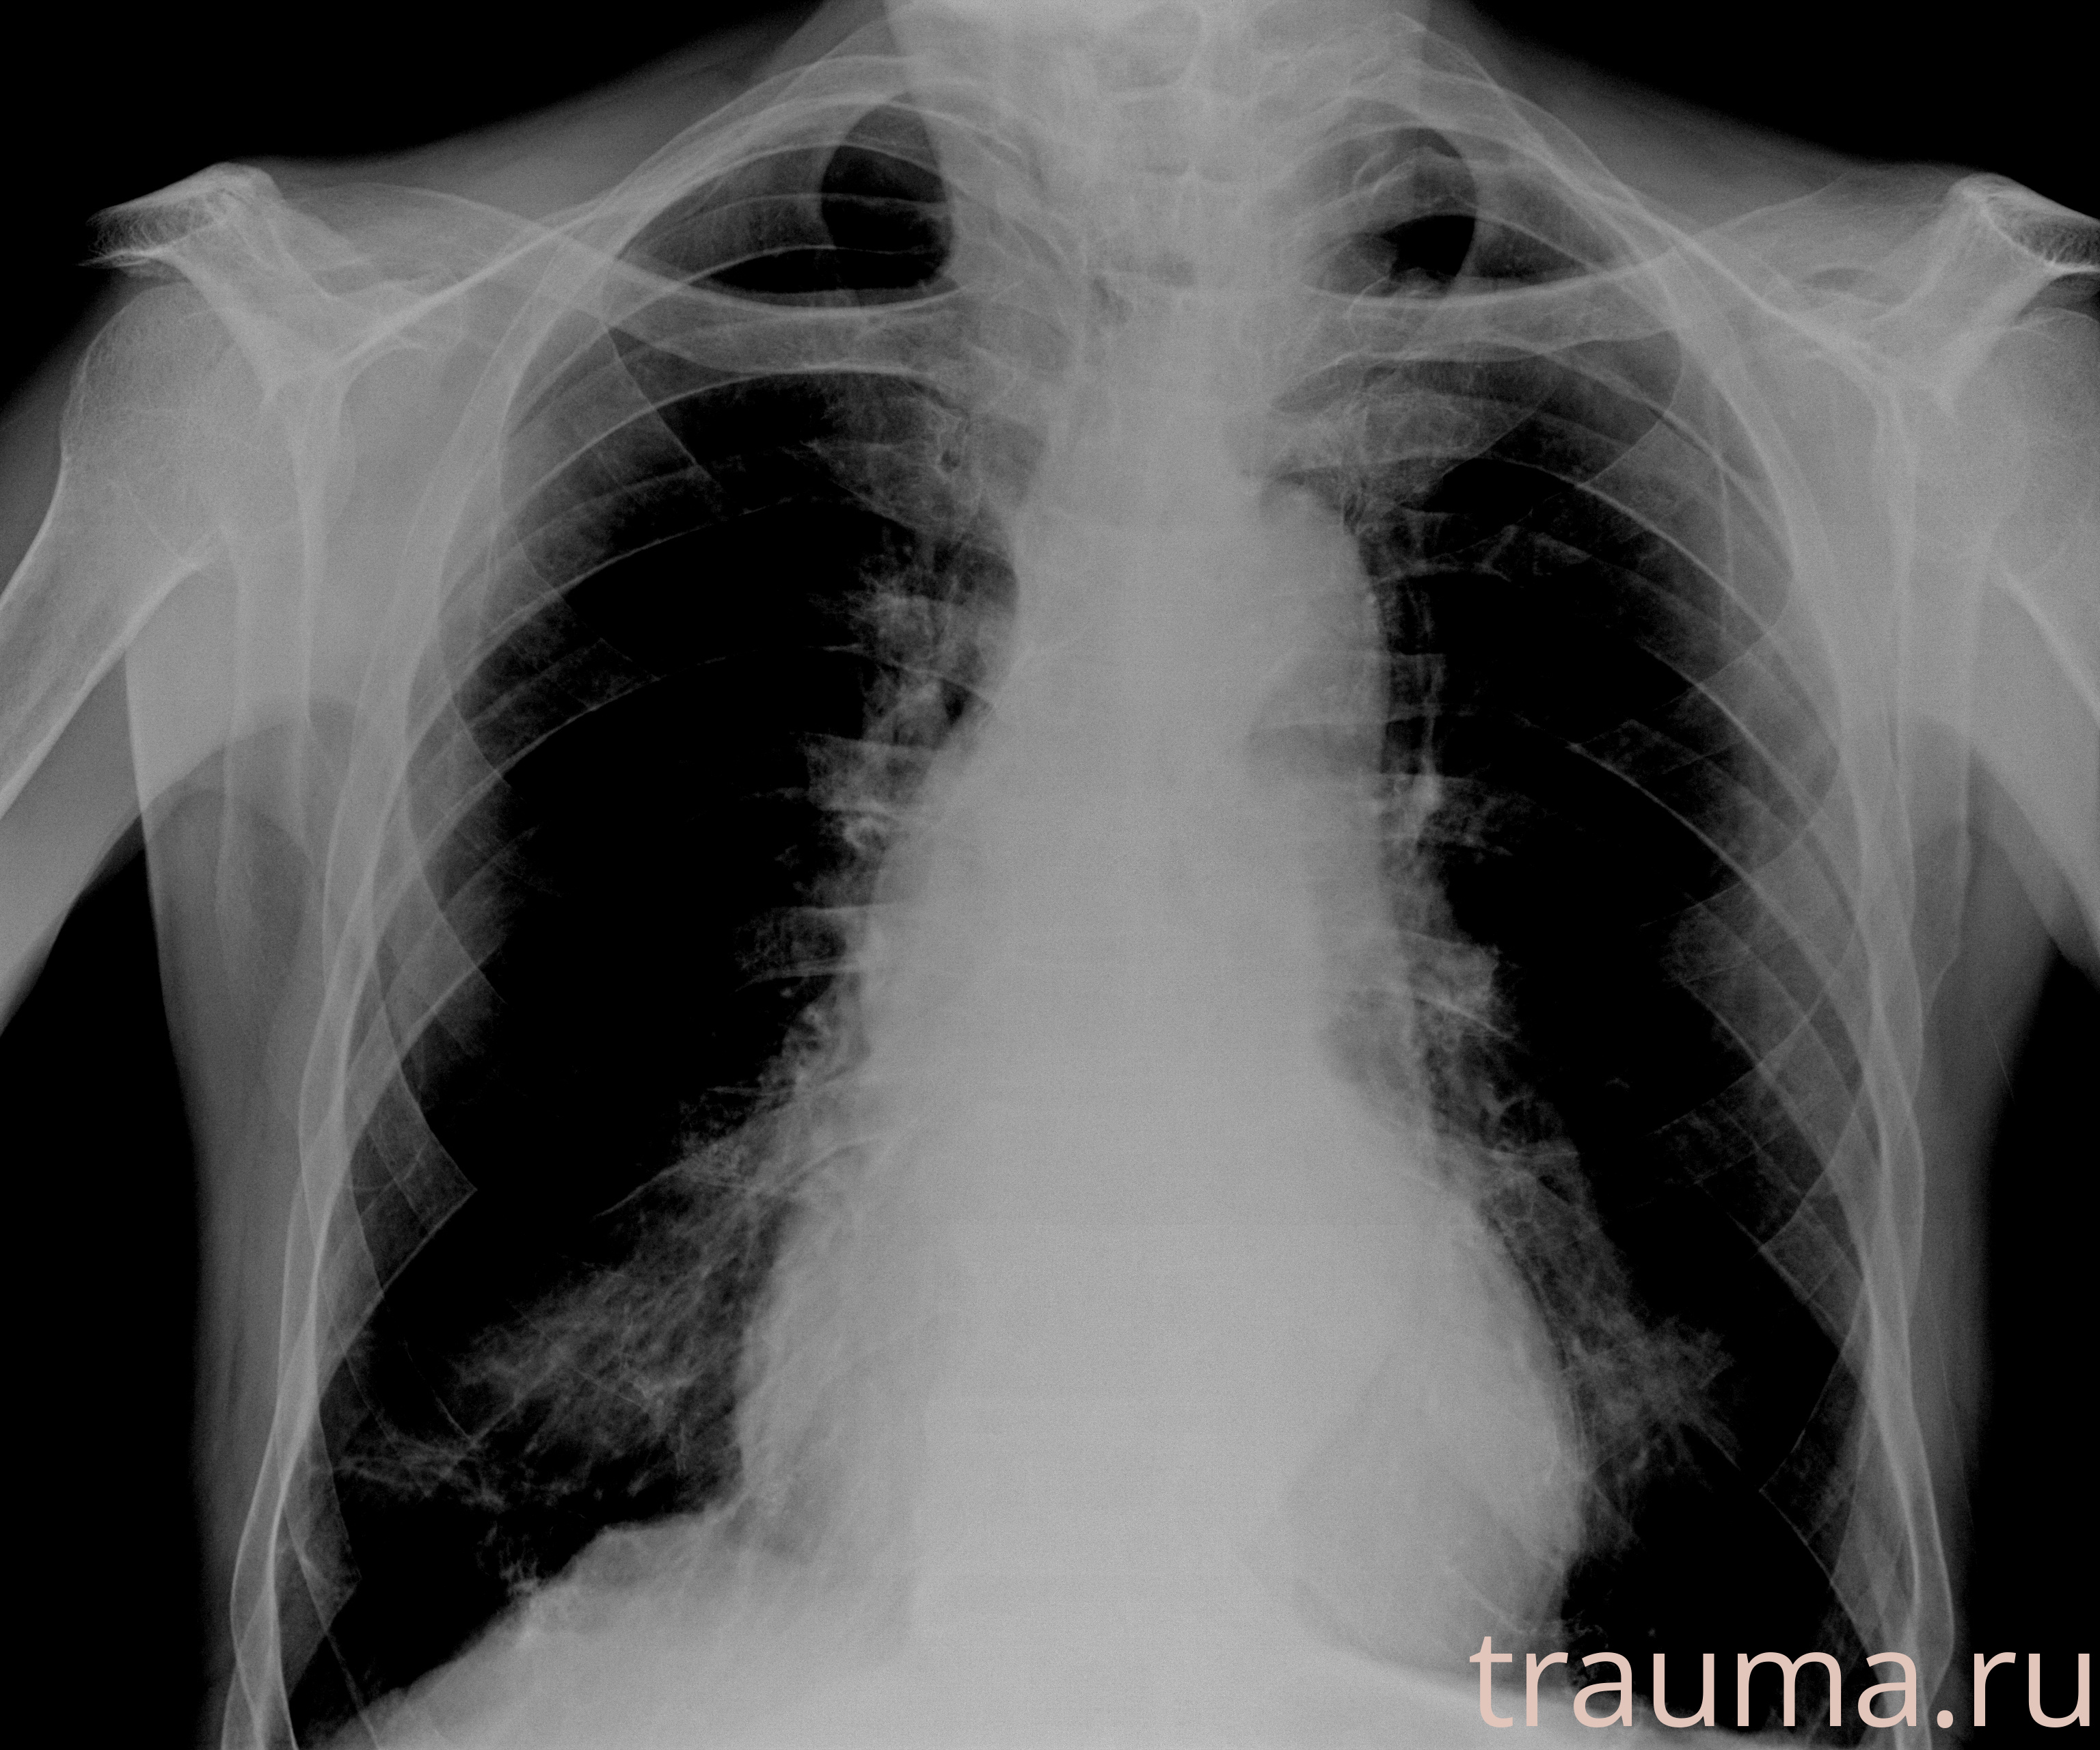

Рентгенограммы

Рентген на дому: по вашему адресу приезжает врач-рентгенолог, травматолог-ортопед с мобильным рентгеновским аппаратом, проводит диагностику травмы или заболевания, делает необходимые рентгенограммы, дает рекомендации по дальнейшему лечению. Получить качественные снимки в домашних условиях возможно благодаря уникальной методике, разработанной МосРентген Центром для института  Склифосовского